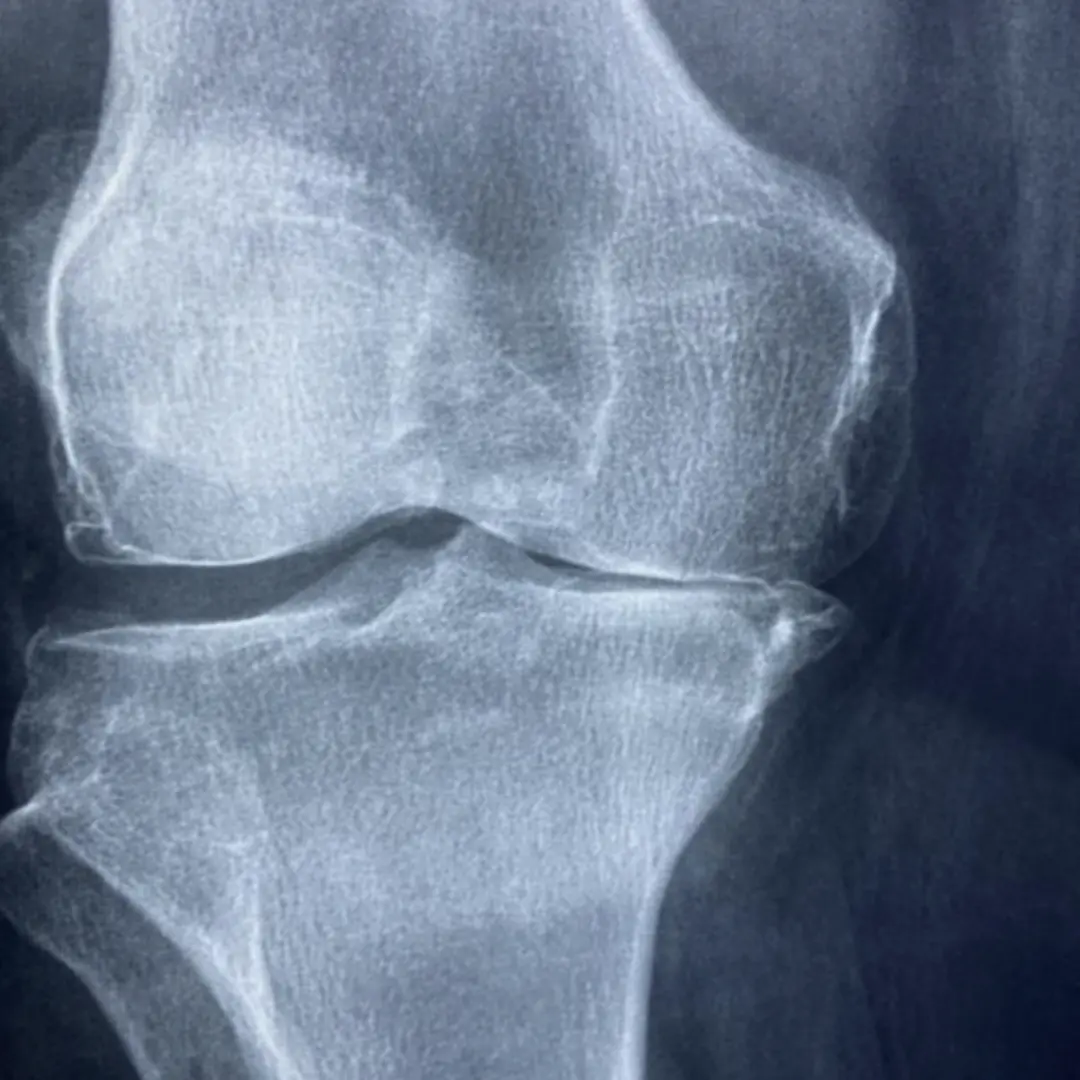

신체 검진을 통해 관절의 붓기, 열감, 운동 범위 등을 확인하기도 합니다. X-ray 검사는 관절의 변형이나 연골 손상 정도를 파악하는 데 기본적인 검사입니다. 필요에 따라 MRI(자기공명영상)나 CT(컴퓨터 단층 촬영) 등의 영상 검사를 추가적으로 시행하여 더욱 자세한 관절 상태를 확인할 수 있습니다. 혈액 검사를 통해 염증 수치나 류마티스 인자 등을 확인하여 류마티스 관절염과 같은 특정 질환을 감별하기도 합니다. 관절액 검사는 관절 내 액체를 채취하여 염증 세포나 결정체 등을 확인하는 방법입니다.